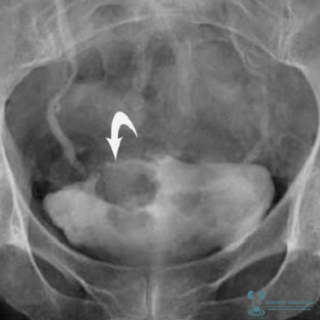

URO TAC y UIV

Ambos estudios son mucho más eficaces para determinar la afección de la vía urinaria superior, pero su uso en general quedará restringido a aquellos casos en que exista una alta sospecha de cáncer de vía urinaria por persistencia de hematuria, o citología de orina positivas sin otras causa demostrable. Aún así son también capaces de detectar el tumor vesical.

MU POINT

La incidencia de Carcinoma Urotelial de Vía Urinaria Superior es de un 1,8 % y se incrementa a 7,5 % en tumores localizados en el trígono.